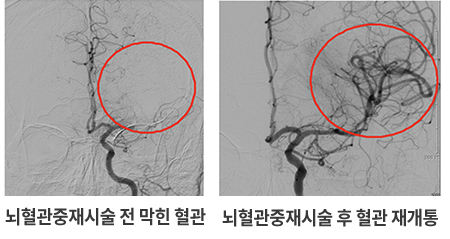

• 뇌혈관 중재치료

스텐트삽입술 : 스텐트삽입술은 혈관 내에 삽입하는 철망을 가르키는 단어로 좁아진 혈관 속에 스텐트를 삽입하여 넓히는 시술입니다.

풍선확장술 : 뇌혈관조영술을 시행하면서 풍선카테터를 삽입합니다. 삽입된 풍선이 부풀어 막혀있던 동맥벽에 압력을 가하게 되어 좁아진 혈관을 넓혀줍니다.

뇌혈관중재시술 전후 이미지